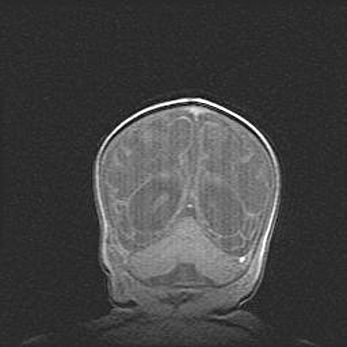

Наружная гидроцефалия с возможной атрофией височных областей.

Возраст: 28 дней

Вес: 3670 г

Пол: мужской

Окружность головы: 38 см

Срок гестации: 40 недель

Гидроцефалия головного мозга у новорожденных – это заболевание, которое характеризуется скоплением избыточного количества спинномозговой жидкости в желудочковой системе головного мозга в результате затруднения её перемещения от места выработки к месту поглощения в кровеносную систему или вследствие нарушения абсорбции. При открытой наружной форме гидроцефалии у новорожденных расширяются и переполняются субарахноидные пространства.

При нормотензивных  формах,  которые,  как  правило,  являются  следствием  перенесенных ишемических  повреждений  паренхимы  мозга,  возможно  сочетание микроцефалии  с нормотензивной гидроцефалией. В основе данных изменений лежит атрофия больших полушарий с преимущественной  локализацией  в  лобно-височных  областях.